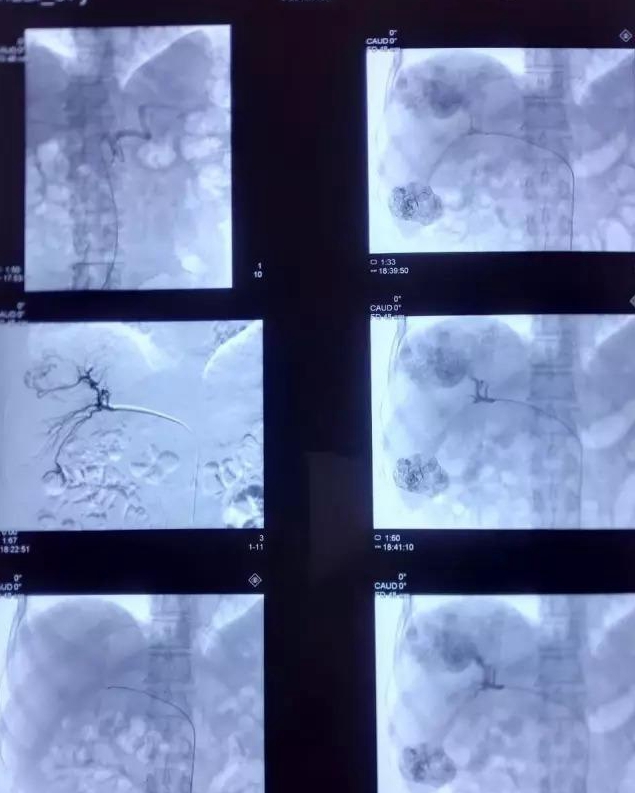

肝癌介入治疗,是指经股动脉插管将抗癌药物或栓塞剂注入肝动脉的一种区域性局部化疗,是非开腹手术治疗肝癌的选择方法。我们经常说的肝癌介入治疗是一种血管介入治疗,可以通过栓塞把肿瘤血管堵住,使肿瘤坏死缺血缩小,或者,通过介入方法局部灌注化疗药物,使其在肿瘤区域局部药物浓度很高,从而达到治疗的目,同时,还可以联合一些射频消融等治疗方式提高治效果果。介入治疗是在局麻状态下进行,创伤小,恢复快,效果好。

循证医学证据业已表明肝癌介入治疗能有效控制肝癌生长,明显延长患者生存期,使肝癌患者获益,已成为不能手术切除的中晚期肝癌重要的治疗方法。